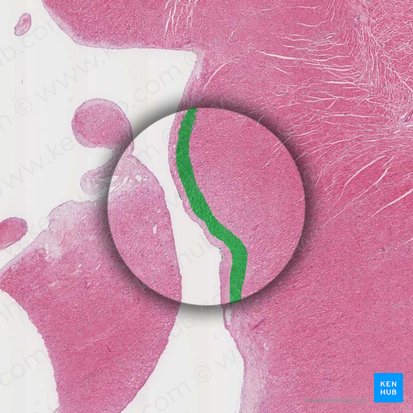

Chordales Endokard

Da die Chordae tendinae aus embryonalem Myokard hervorgehen, weicht ihr Aufbau vom restlichen Endokard ab. In dickeren Chordae kann daher gelegentlich Herzmuskulatur gefunden werden.

Subendothelial finden sich elastische Fasern, über das gesamte Stroma verteilt sind die Kollagenfasern wie eine Sehne parallelfaserig angeordnet. Diese sind im entspannten Zustand gewellt, was durch den Verkürzungszug der elastischen Fasern bedingt ist. Das ermöglicht eine Längenänderung von 10 bis 20% während der Herzaktion.

Das Gewebe ist frei von Blutgefäßen und glatter Muskulatur. Die Kollagenfasern spalten sich in den Papillarmuskeln in zipfel- und blattförmige Formierungen und verankern sich im Endomysium.